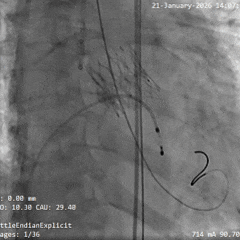

术中影像

根部造影

瓣叶活动差,可见明显反流,猪尾导管测量跨瓣压差约50mmHg

20mm球囊预扩

微腰微漏,左右冠均显影

造影确认瓣环与瓣膜位置

瓣膜0位初始定位释放,展开过程微微下移

全展开位造影评估

瓣膜呈直筒型,微腰,大弯侧约瓣下3mm,少量反流,冠脉显影

瓣膜无张力脱钩

植入后造影评估

瓣膜位置合适,可见少量反流

多角度造影评估

瓣膜形态可,冠脉显影,猪尾测量压差为0